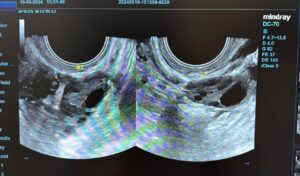

O tânără de 21 de ani a mers la medic din cauza unor dureri și a dereglărilor menstruale și a avut un șoc. A aflat că are un chist hemoragic de cm la nivelul ovarului drept. Aceasta a mers la medicul Alexandra Ciobanu, în luna ianuarie, cu „dereglări ale ciclului menstrual și dureri pelvine”.

Doctorul i-a dat să urmeze un tratament pentru cinci luni, pe care aceasta l-a urmat cu strictețe, iar rezultatele nu au întârziat să apară.